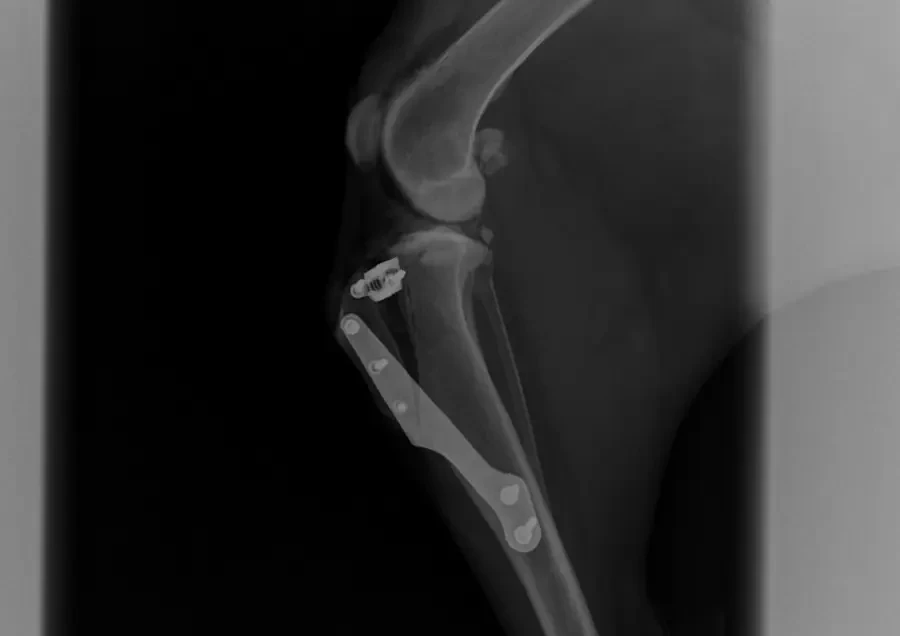

Zerwanie więzadła krzyżowego doczaszkowego jest jedną z najczęstszych przyczyn wizyt w zakładach leczniczych z powodu kulawizny u psów. Cele tego artykułu to:…

Zerwanie więzadła krzyżowego do czaszkowego jest jedną z najczęstszych przyczyn wizyt w zakładach leczniczych z powodu kulawizny u psów. Celem tego artykułu…